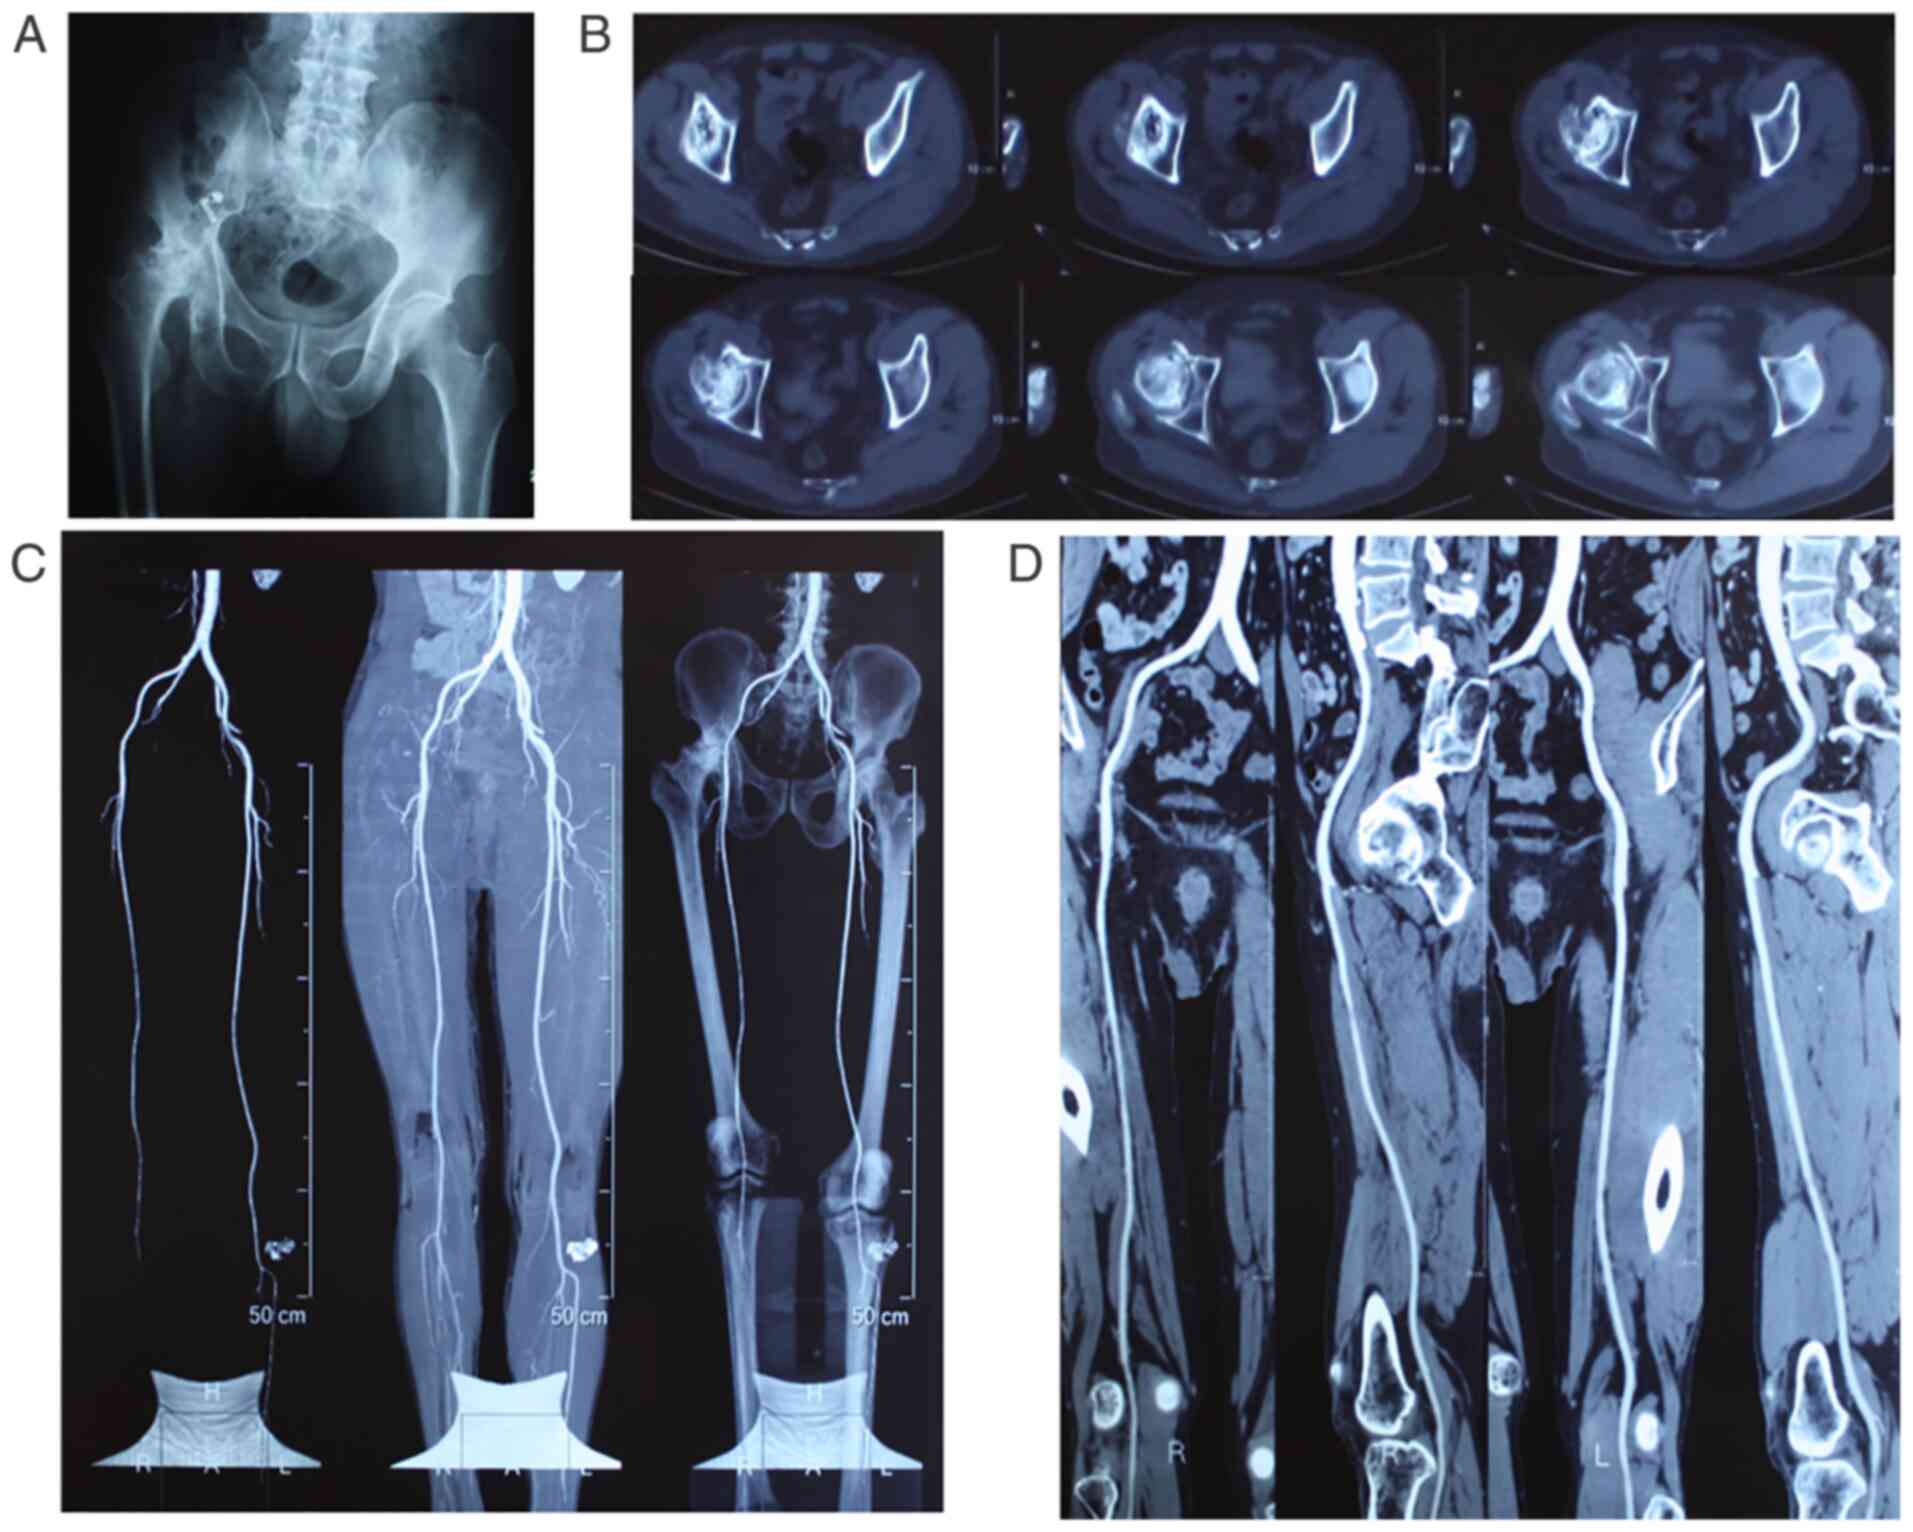

Non-traumatic osteonecrosis of the femoral head (NONFH) is the result of impaired blood supply to the femoral head and structural and functional disruption of local articular cartilage, subchondral bone and blood vessels (Fig. 1), which culminate in subchondral osteonecrosis, femoral head collapse and hip joint pain (1). Mont et al (2) estimate that the total number of patients with NONFH worldwide could reach >20 million in the next decade. The pain and limited hip joint mobility resulting from femoral head necrosis can seriously affect the quality of life of the patient.

Figure 1

Imaging results of non-traumatic femoral head necrosis. (A) Representative X-ray showing lack of any joint space in the right hip joint and collapse of the acetabulum and femoral head, along with altered structure. (B) Representative computerized tomography image showing stenosis of the hip joint space, hollow femoral head and abnormal calcification. (C) Angiography of the lower extremities showing insufficient supply from blood vessels in the right femoral head. (D) Angiography of one side of the lower extremity showing properly functioning main blood vessels.